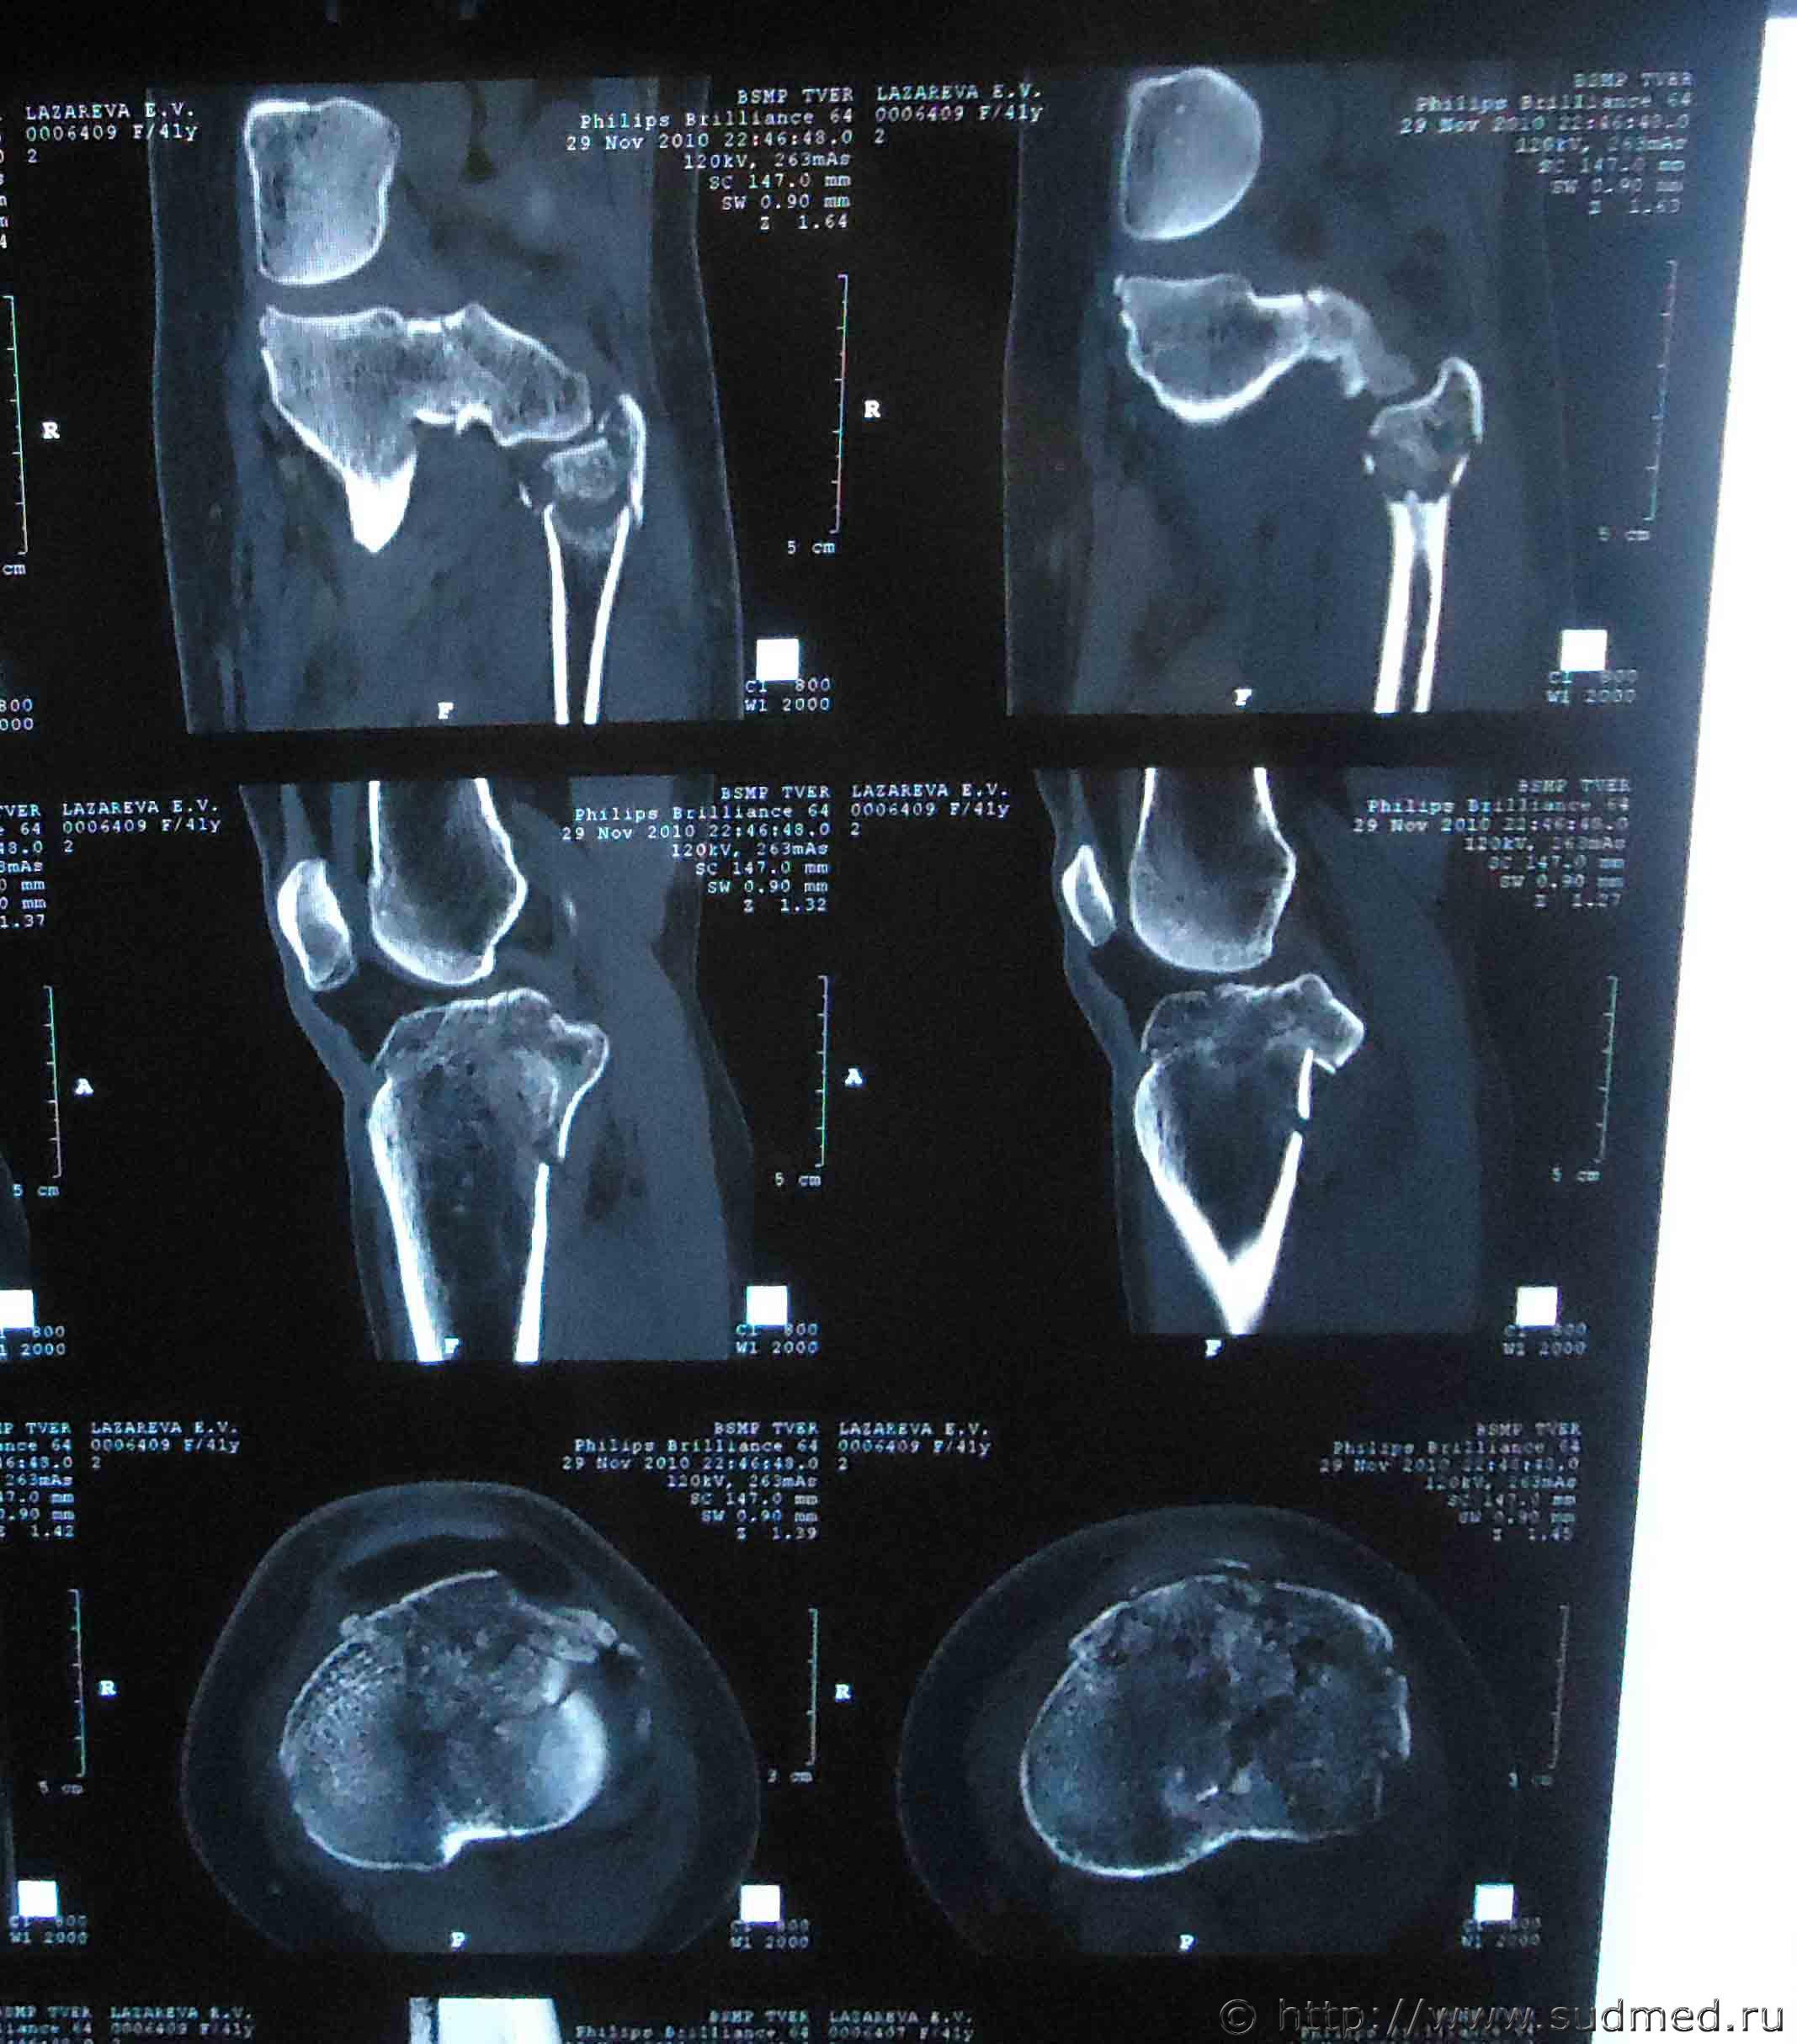

Здравствуйте. На мою жену 2 года назад был совершен наезд, при этом она получила травмы: ЗЧМТ, сотрясение головного мозга, закрытый оскольчатый внутрисуставной перелом проксимального метаэпифиза левой большеберцовой кости со смещением, закрытый оскольчатый перелом проксимального эпифиза левой малоберцовой кости без смещения, закрытый косой перелом правой ключицы средней трети со смещением отломков.

Помогите установить степень тяжести вреда и что делать для обжалования медицинской экспертизы? Снимки прилагаю